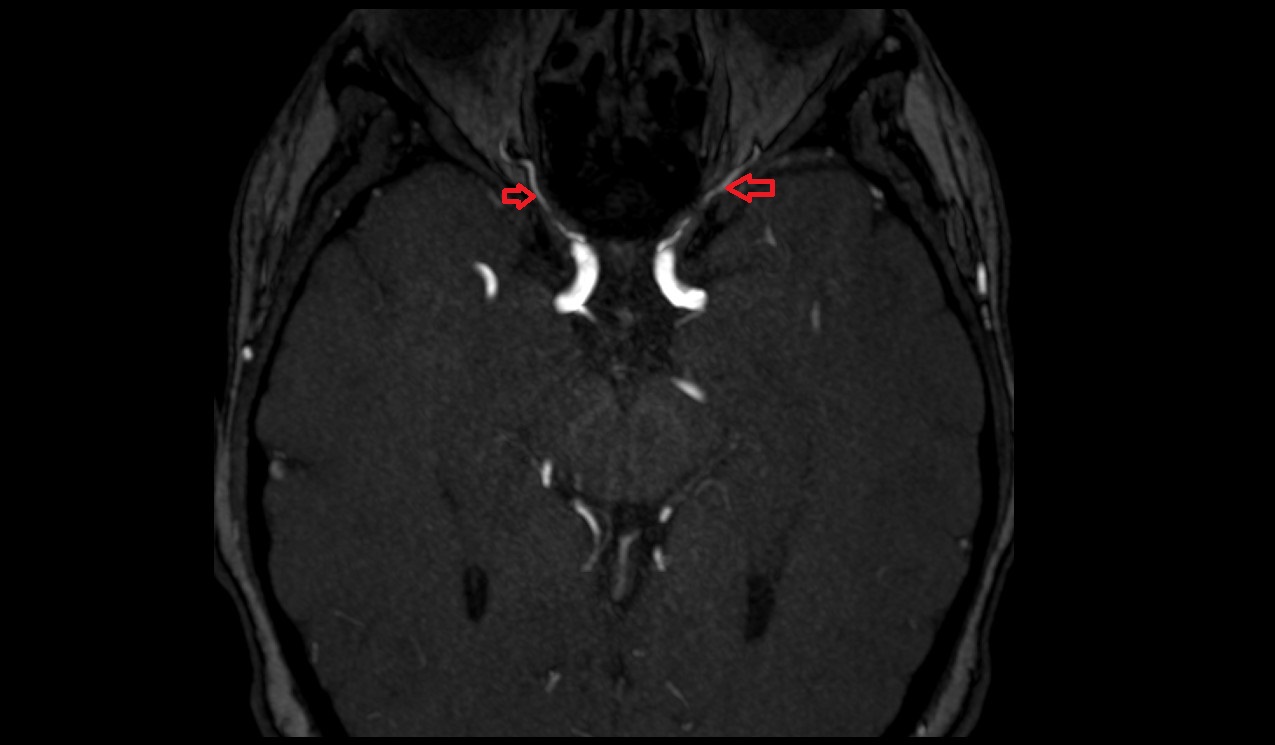

- Lateral aperture of fourth ventricle (foramen of Luschka)